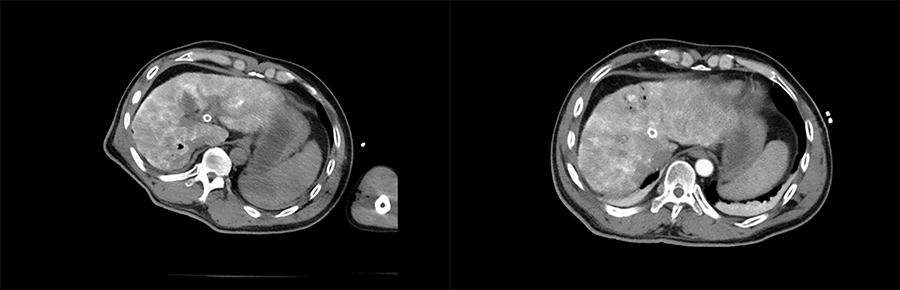

▲ 患者一术后影像

▲ 患者二术后影像